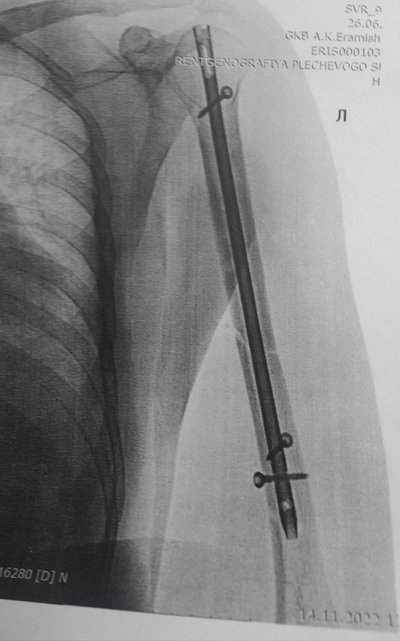

У меня оскольчатый фрагментарный перелом диафиза бедра со смещением отломков. Шрамов теперь ояебу. Помимо шрама на ноге, шрам от полостной операции на животе, страшенные шрамы на коленях, на плече, на боках. Так что, у тебя ещё не так всё плохо:) мне всё тело забивать тату придётся